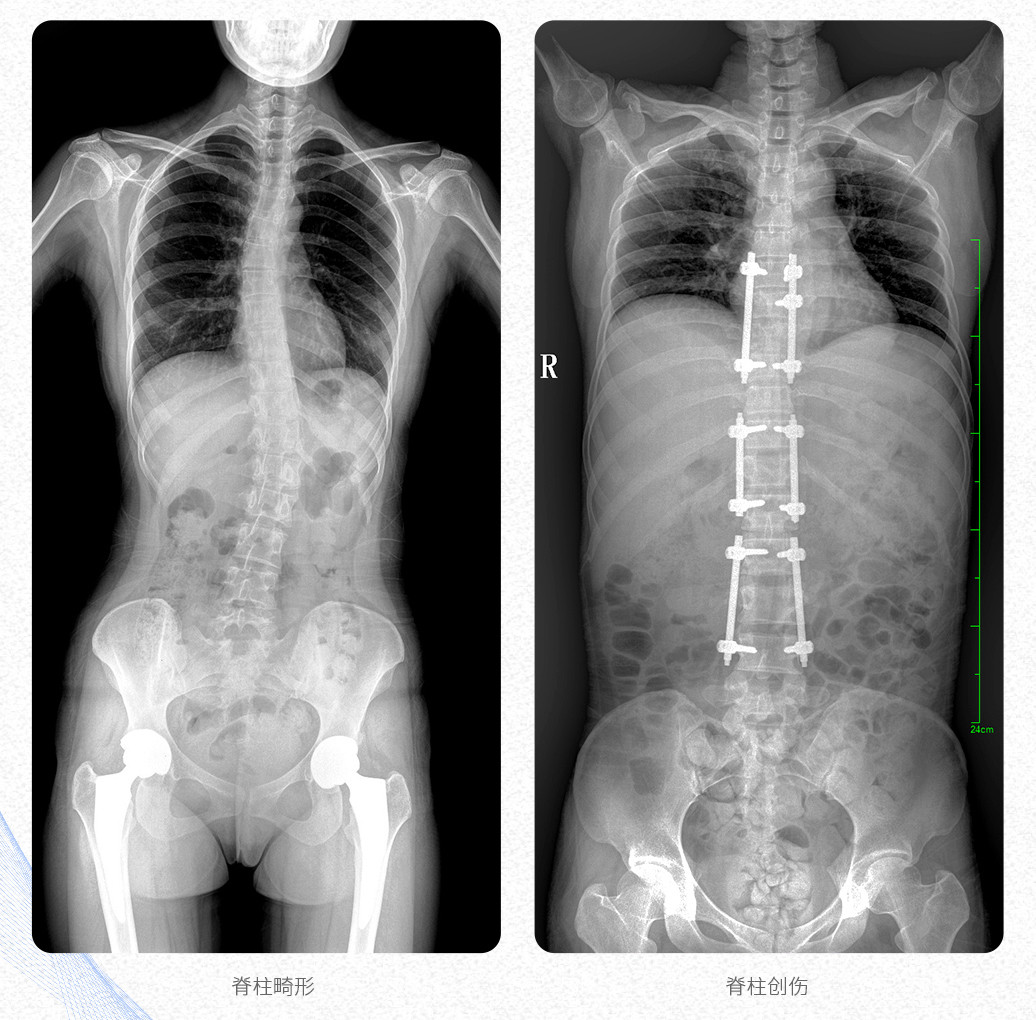

新品PLX8600大視野平板動(dòng)態(tài)DR產(chǎn)品說(shuō)明:

? ? 普愛(ài)醫(yī)療新推出自主研發(fā)的大視野平板動(dòng)態(tài)DR——PLX8600,專為臨床大視野需求打造,圖像不拼接,可有效簡(jiǎn)化影像科室檢查流程,提升工作效率,提高診斷精度,降低臨床拍攝劑量。